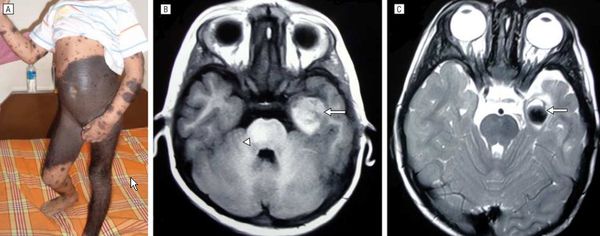

Нейрокожный меланоз

В редких случаях развивается нейрокожный меланоз — заболевание, при котором меланоциты разрастаются в центральной нервной системе. К таким нарушениям может приводить мутация гена BRAF [50] .

Факторы риска развития нейрокожного меланоза:

- гигантский невус на спине (более 40 см);

- множественные невусы-спутники — чем их больше, тем выше риск;

- более двух средних невусов, особенно если помимо них много других невусов.

Болезнь тяжелее переносят дети младше 10 лет.

В исследовании американских учёных меланоз диагностировали у 26 из 379 пациентов с большими врождёнными невусами [12] . Заболевание может протекать без симптомов и случайно выявляться при МРТ, но в некоторых случаях оно сопровождается неврологическими нарушениями:

Неврологические симптомы могут развиться из-за кровоизлияния в желудочки головного мозга, нарушения циркуляции спинномозговой жидкости, сдавления спинного мозга или злокачественного перерождения меланоцитов [3] [14] .

- МРТ головного и спинного мозга с контрастированием гадолинием и дальнейшая оценка результатов в экспертном центре.

МРТ головного и спинного мозга с контрастированием гадолинием обязательна для детей с высоким риском меланоза и неврологическими симптомами. В некоторых исследованиях при высоком риске меланоза рекомендовано делать МРТ в первые полгода жизни, даже если нет неврологических симптомов [15] .

Если большой невус расположен вдоль позвоночника или его окружают многочисленные невусы-спутники, МРТ проводят до четырёхмесячного возраста [35] .